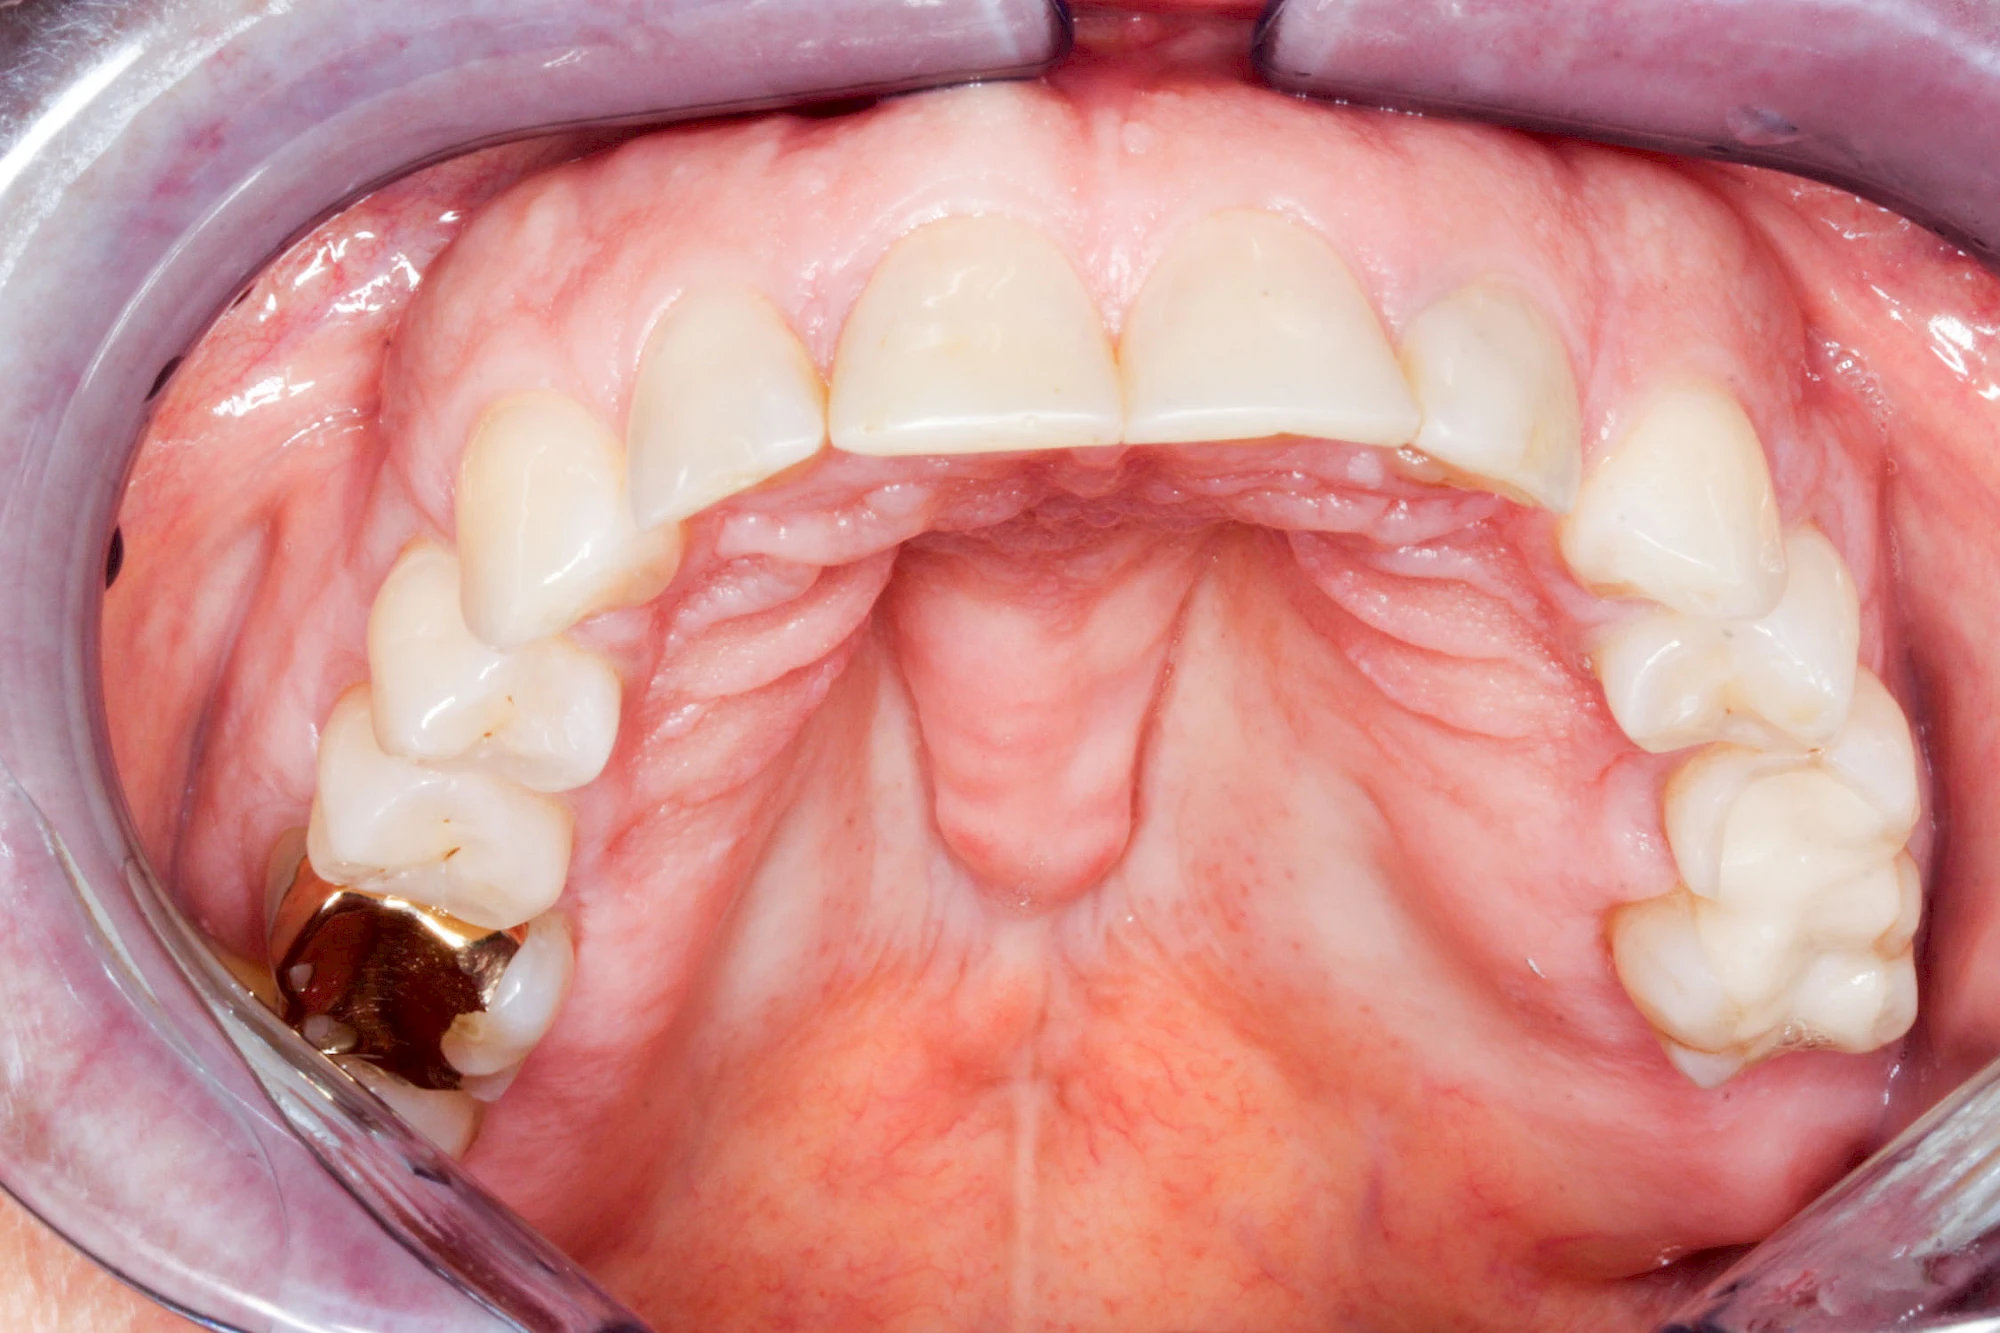

Überbeine im Bereich der Kiefer sind gar nicht so selten. Häufiger im Bereich der Seitenzähne unterhalb des Zahnfleisches, aber auch in der Mitte vom Gaumen. Überbeine haben in dem Sinne keinen Krankheitswert, müssen also nicht operativ entfernt werden, wenn diese nicht stören. Überbeine können ein Anzeichen für Knirschen und Pressen sein.